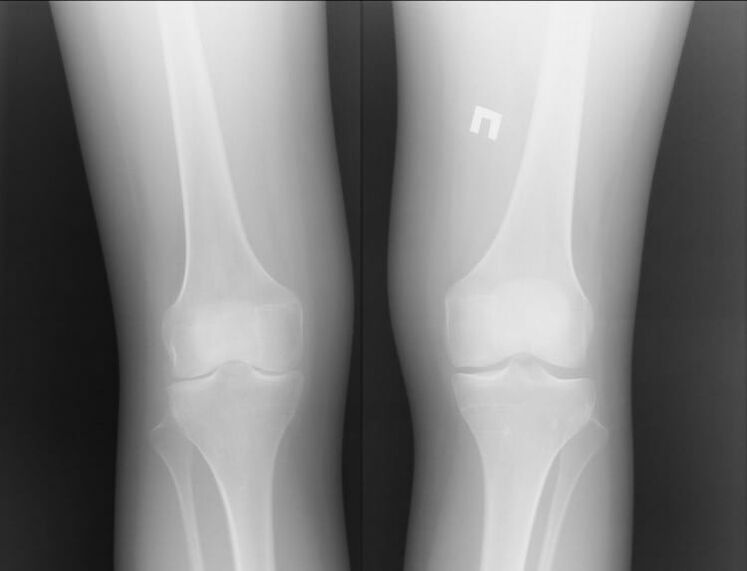

Arthrose ist eine Gelenkerkrankung, die durch Knorpelprobleme verursacht wird. Sie beginnen sich allmählich aufzulösen und zu brechen, was zu unerträglichen Schmerzen führt. Es kommt sowohl in akuten als auch in langfristigen Formen vor. Es tritt häufig morgens oder nach schwerer körperlicher Aktivität auf.

Symptome einer Arthrose

Arthrose ist größtenteils eine chronische Erkrankung. Möglicherweise verstehen Sie sehr lange nicht, dass Sie an dieser Krankheit leiden, da sie sich in Form vorübergehender schmerzender Schmerzen äußert. Es kann jedoch entweder schnell oder langsam auftreten. Wird eine Arthrose nicht rechtzeitig im Frühstadium erkannt, führt diese Erkrankung zu einer Behinderung. Symptome einer Arthrose:

- Schwellung im periartikulären Bereich. Bei Arthrose ist die Situation anders: Das Gelenk schwillt nur im akuten Krankheitsfall an. Die Erkrankung geht mit starken Schmerzen einher.

- Knirschen und Brüchigkeitsgefühl im Gelenk. Von den ersten Minuten an stört das Knirschen den Besitzer nicht besonders, aber wenn keine Behandlung erfolgt, wird es von anderen gehört. Nach dem Duschen oder Schwimmen in kühlem Wasser tritt häufig ein Gefühl der Brüchigkeit auf.

- Ziehschmerz. Dies gilt insbesondere dann, wenn das betroffene Gelenk belastet wird. Zum Beispiel beim Treppensteigen.

Meistens entsteht Arthrose durch schwere Belastungen oder Verletzungen. Der schmerzende Schmerz kann sich nachts verstärken und bis zum Morgen anhalten.